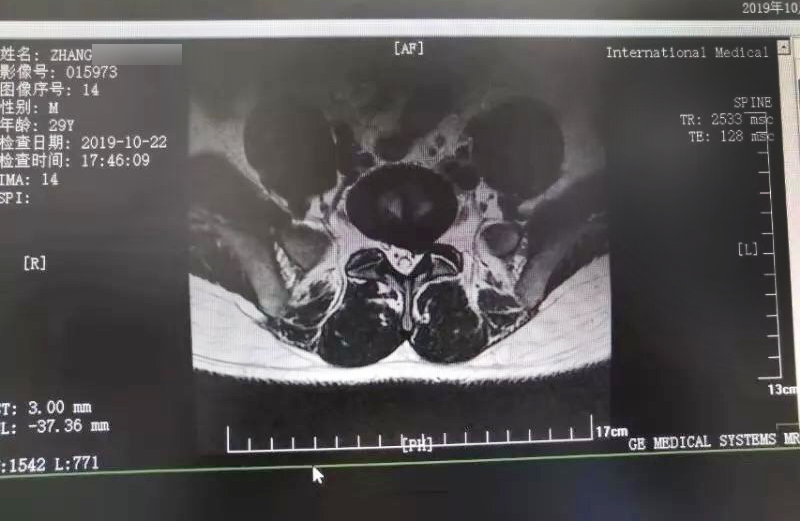

三秦網(wǎng)報道—西安國際醫(yī)學中心骨科醫(yī)院成功完成首例椎間孔鏡手術。點擊閱讀。